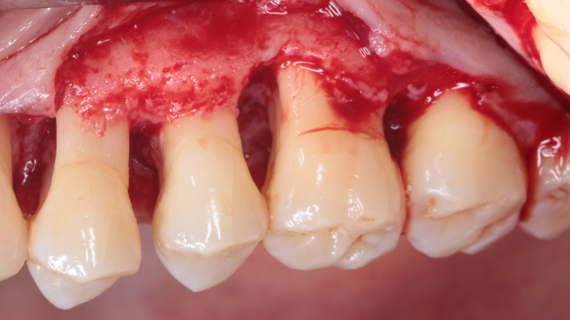

A doença periodontal é uma doença infeciosa, que se caracteriza pela progressiva perda de inserção gengival e destruição do tecido ósseo adjacente. A evolução deste processo pode levar à perda dentária.

O objetivo principal do tratamento da doença periodontal consiste em reestabelecer a saúde do periodonto, através da redução ou remoção de espécies periodontopatogênicas das superfícies dentárias e a recuperação da estrutura e função dos tecidos periodontais perdidos.

As técnicas convencionais de tratamento da doença periodontal, tanto cirúrgicas como não cirúrgicas, poderão levar a uma redução das bolsas periodontais, impedindo a progressão da doença.

Os procedimentos cirúrgicos clássicos permitem, através de um bom acesso às superfícies radiculares, uma eficaz redução das bolsas periodontais com melhoria da arquitetura óssea peridentária.

Nas últimas décadas, a comunidade científica tem procurado desenvolver novos materiais de regeneração e novas técnicas cirúrgicas que permitam regenerar o periodonto de uma forma previsível.

Esta apresentação irá focar-se na literatura existente relativamente à anatomia e cicatrização do periodonto, cirurgia periodontal ressetiva e regenerativa, materiais de regeneração periodontal e complicações.